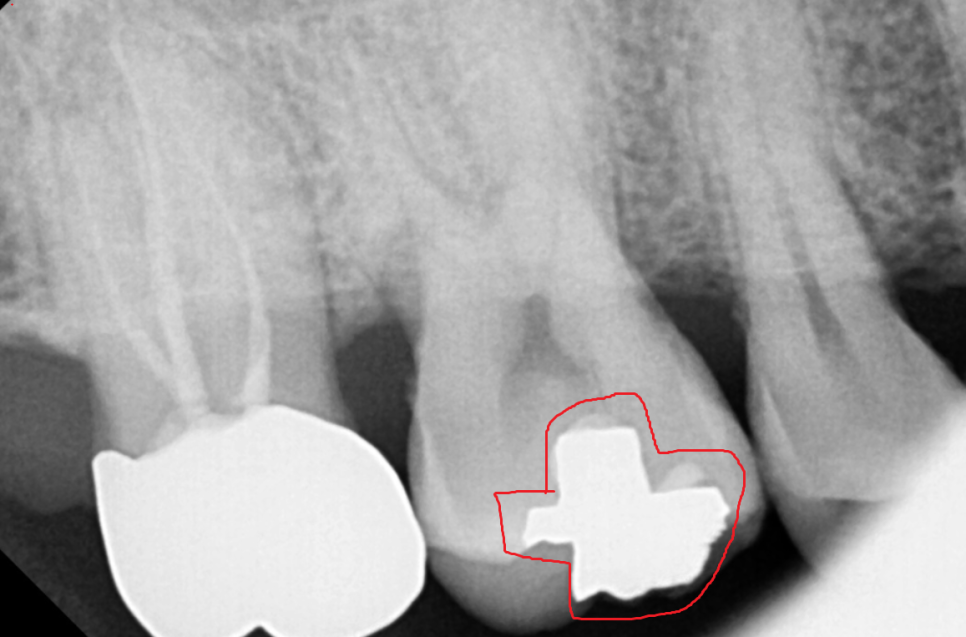

기존에 떼운 주변으로 충치가 관찰되는 경우

사이에 까맣게 비춰보인다거나

충치가 의심될 때에는 x-ray를 찍어서

정확하게 확인해 보아야합니다!

231111

떼운 부분의 깊이도 확인이 가능하고

충치인지 아닌지 판별할 때

x-ray가 아주 도움이 되기 때문이죠.

치아는 하얗게 나와야하는데

충치가 생긴 치아의 경우

내부가 텅 비게되어

까맣게 표시됩니다.

240513

위에 사진처럼 말이에요!